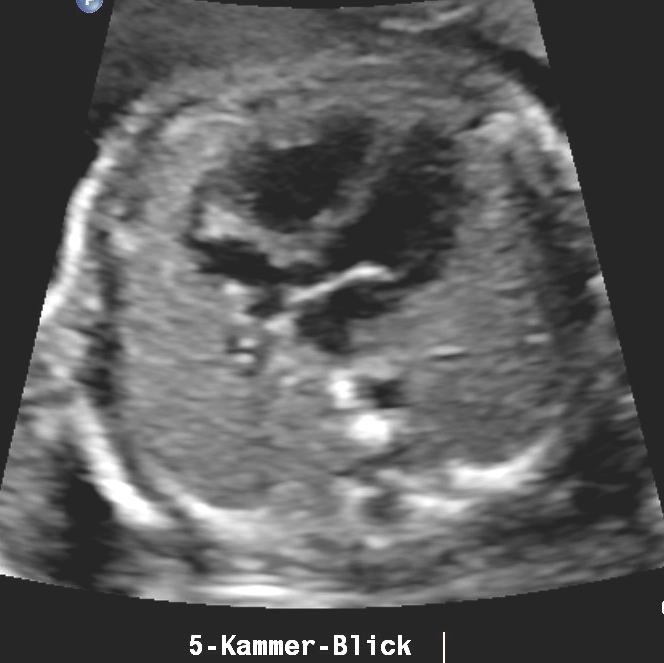

Bildtitel

Button